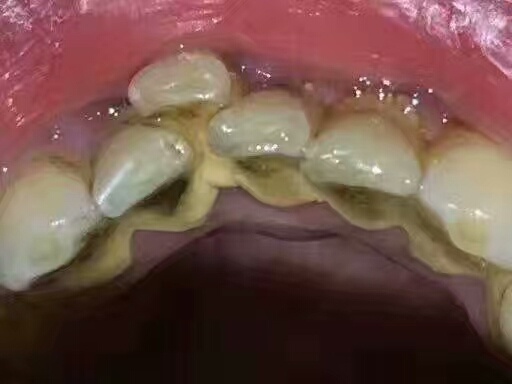

我一开始住在你牙齿表面的时候很低调,你不会痛不会痒,几乎没有感觉哦!根本意识不到我的存在!可是一旦我发展壮大,占领你的口腔,你可能会因为我患上无法根治的牙病!

每次你吃完美食,食物就在口腔里经过牙齿咀嚼并和唾液混合变成细小好消化的糜状物和一部分食物残渣,同时会在你的牙齿周末慢慢形成牙菌斑,对的!牙菌斑就是我的前身哦!

然后,我最好的帮手“钙化”会助我“成型”,牙菌斑和食物残渣在唾液的浸泡下经过24小时会被唾液中的成分钙化,变成初始的牙结石啦!

我最喜欢“热闹”,天天要去刺激一下牙龈,牙龈就会发炎,有时候牙龈内侧还会发生溃疡,你的牙齿就会出现牙龈出血、口臭和牙周感染等。

我不仅是一个硬汉,还是“敌军作战基地”,我会滋生更多牙菌斑同时吸附更多的细菌毒素,我的队伍就会越来越壮大!经过我“日积月累”的努力,你就换上了牙周病,当你的牙周病越来越重!可能就只能拔下这颗牙齿了!这颗牙齿就成为了我的战利品!

我在刚形成的时候还是软垢,使用口腔清洁法或认真刷牙,我都会被消灭!但是一旦我变身成功,也就是钙化了,牙刷就拿我没办法了!你们只能去正规的口腔医院才能甩掉我!千万不要用超声波洗牙,因为我害怕它,它是我的天敌!